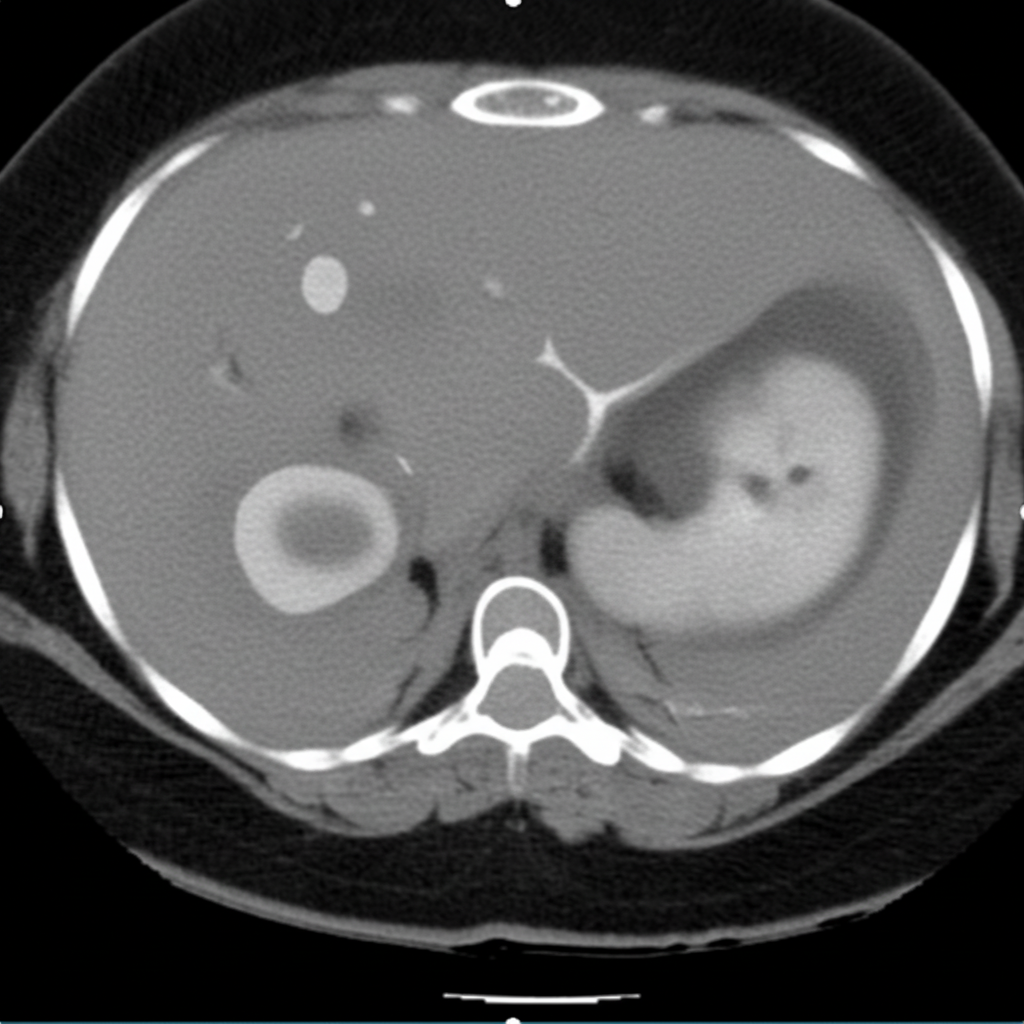

Explanation: ***Amoebic liver abscess*** - Characterized by **"anchovy sauce" pus** - a thick, reddish-brown fluid containing necrotic hepatocytes and blood. - Classic presentation includes **right upper quadrant pain**, fever, and **hepatomegaly** in patients with history of travel to endemic areas. *Lung abscess* - Typically produces **purulent, foul-smelling sputum** rather than the characteristic anchovy sauce appearance. - Chest X-ray shows **air-fluid levels** within lung parenchyma, not hepatic involvement. *Pancreatic abscess* - Associated with **severe epigastric pain** radiating to the back and elevated **serum amylase/lipase**. - Usually occurs as a complication of **acute pancreatitis** and lacks the characteristic anchovy sauce pus. *Subphrenic abscess* - Located in the **subphrenic space** between diaphragm and liver surface, not within liver parenchyma. - Typically follows **abdominal surgery** or **bowel perforation** and contains typical bacterial pus, not anchovy sauce.